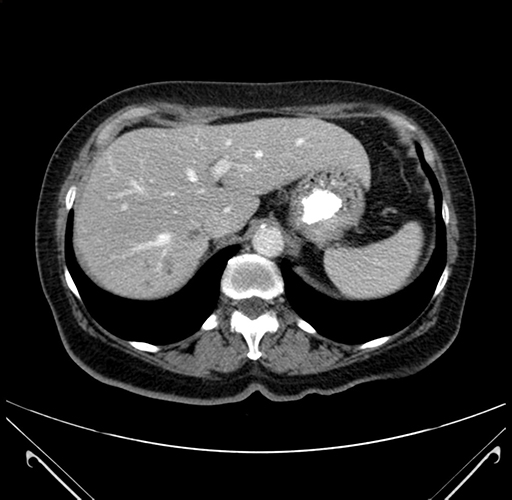

Pre-Chemo: Axial Venous

Axial Venous